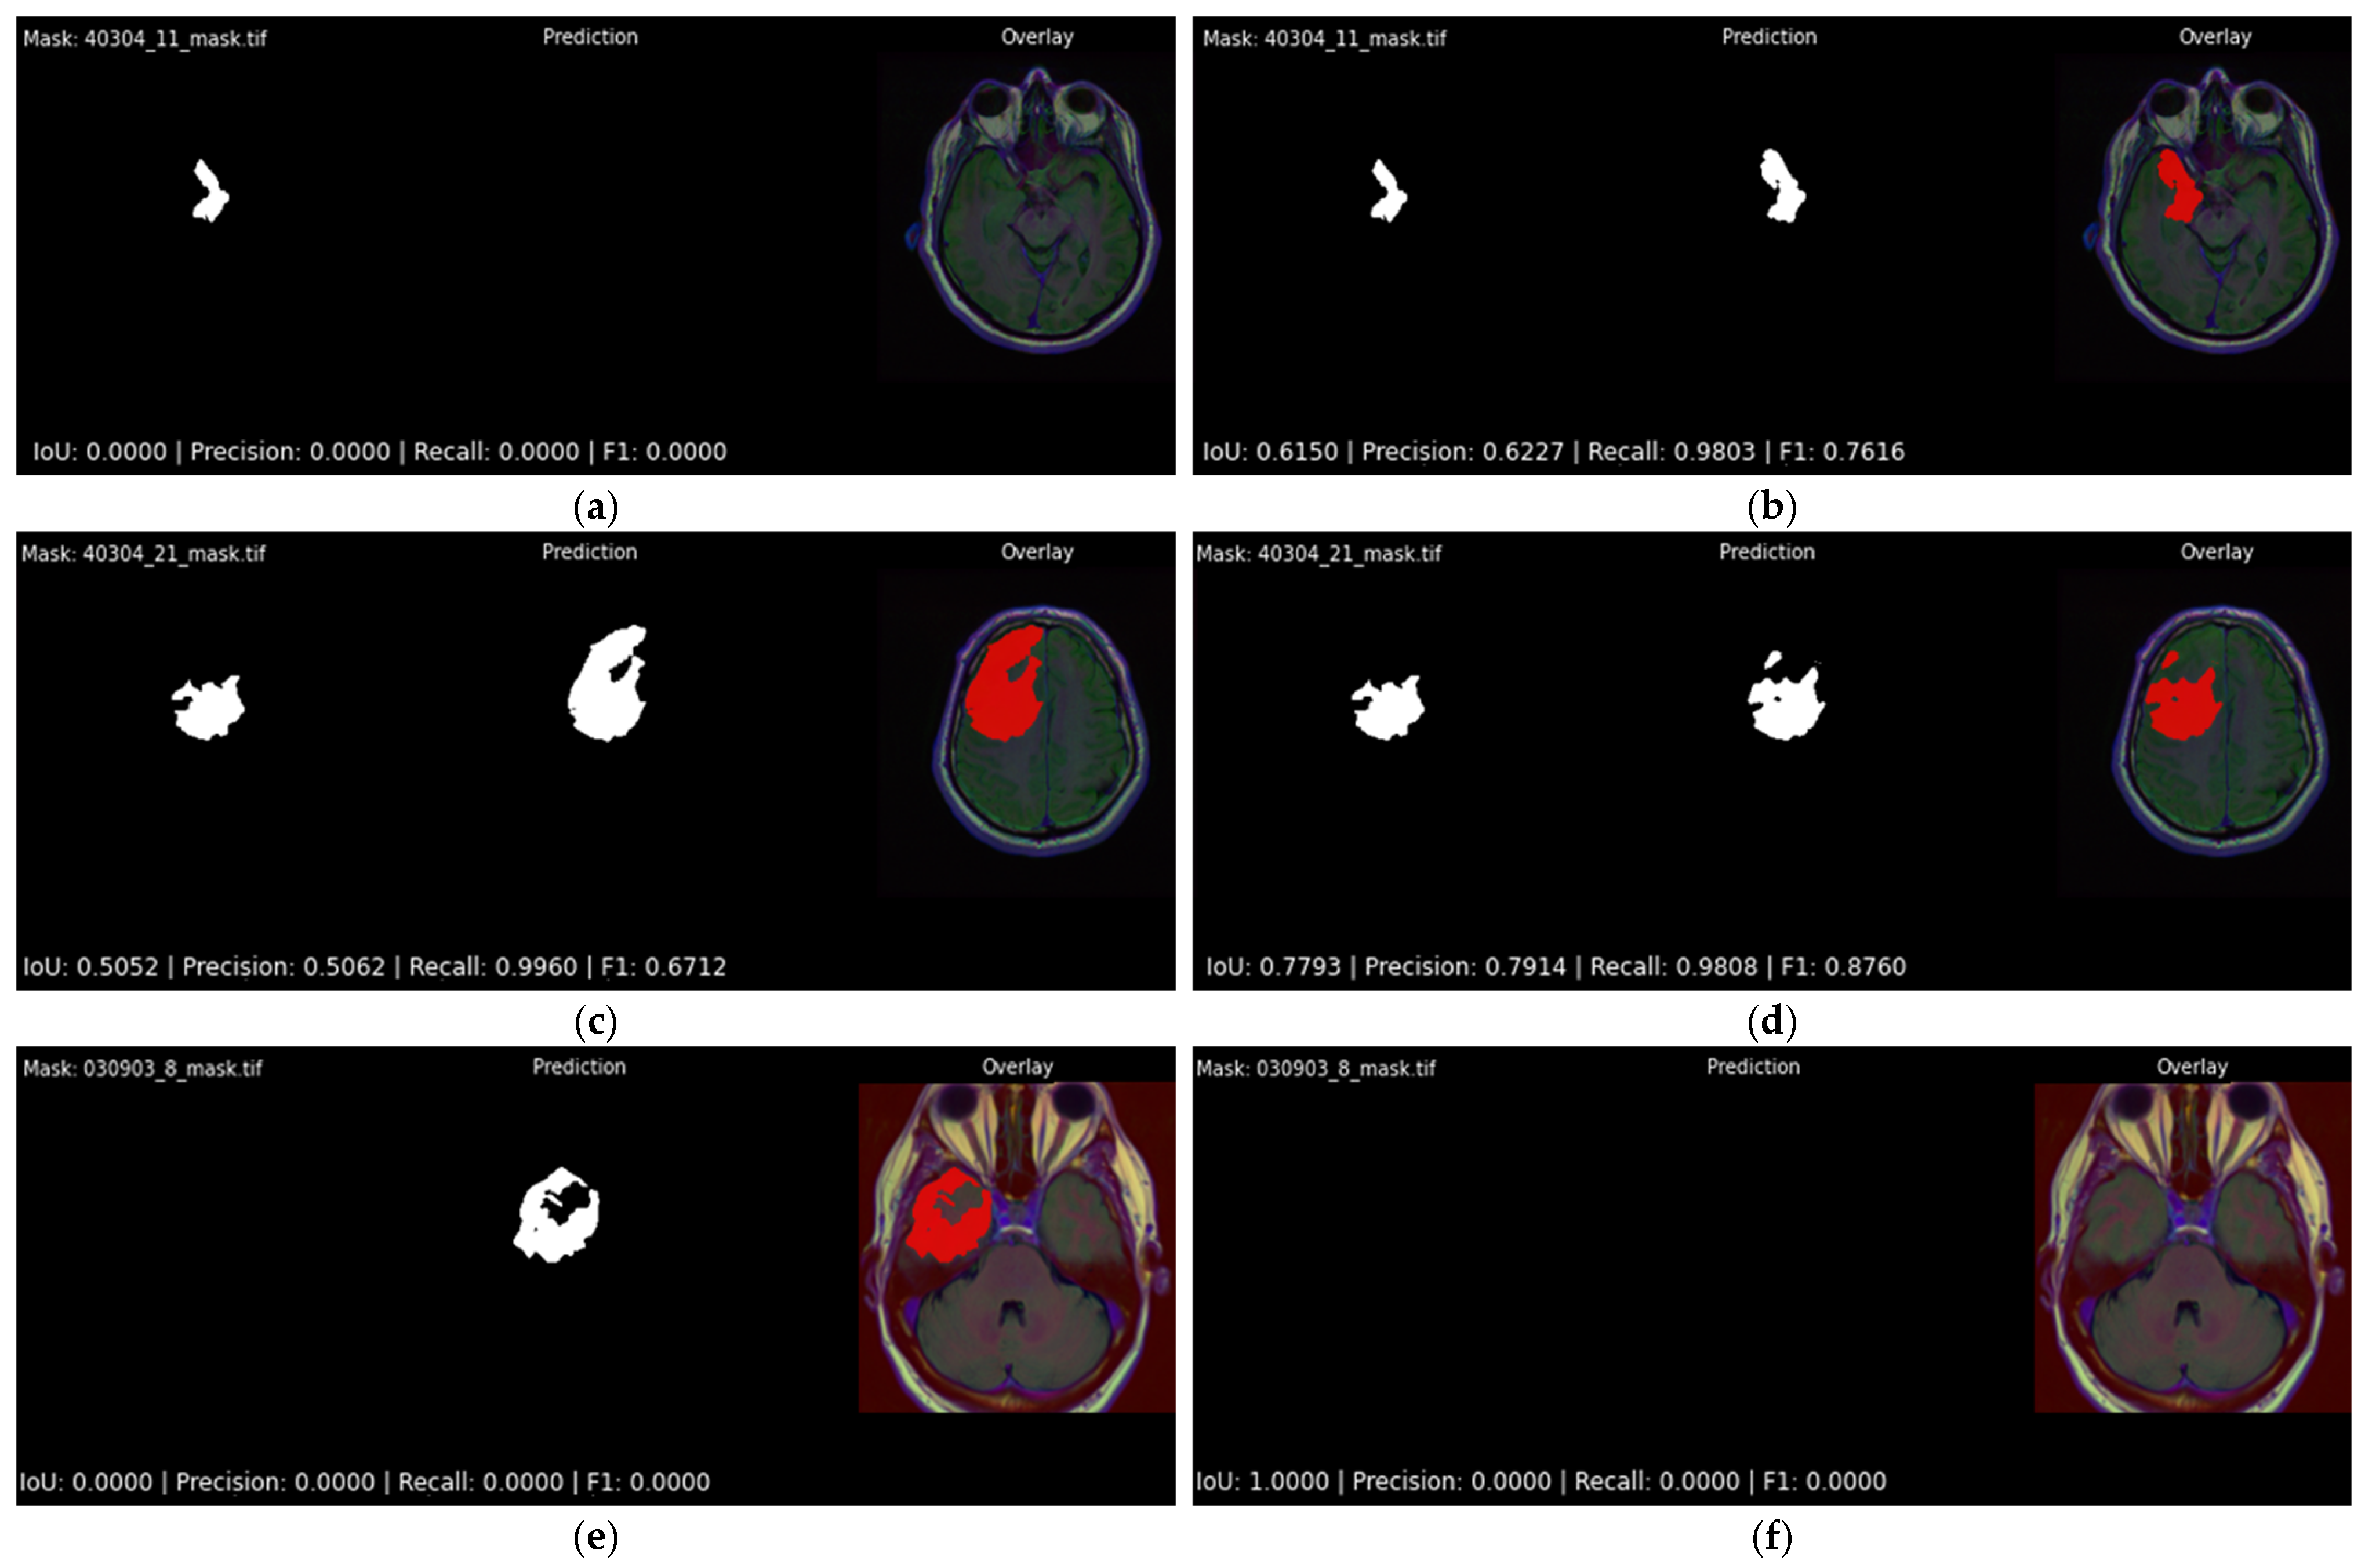

4.1.2. Assessment of Softmax Output Layer Architectures

4.2. Qualitative Results

| Softmax vs Sigmoid | Figure 12 | Softmax detects small lesions missed by sigmoid; prevents false positives in tumor-free slices | 0.615 vs. 0.000; 0.779 vs. 0.505 |